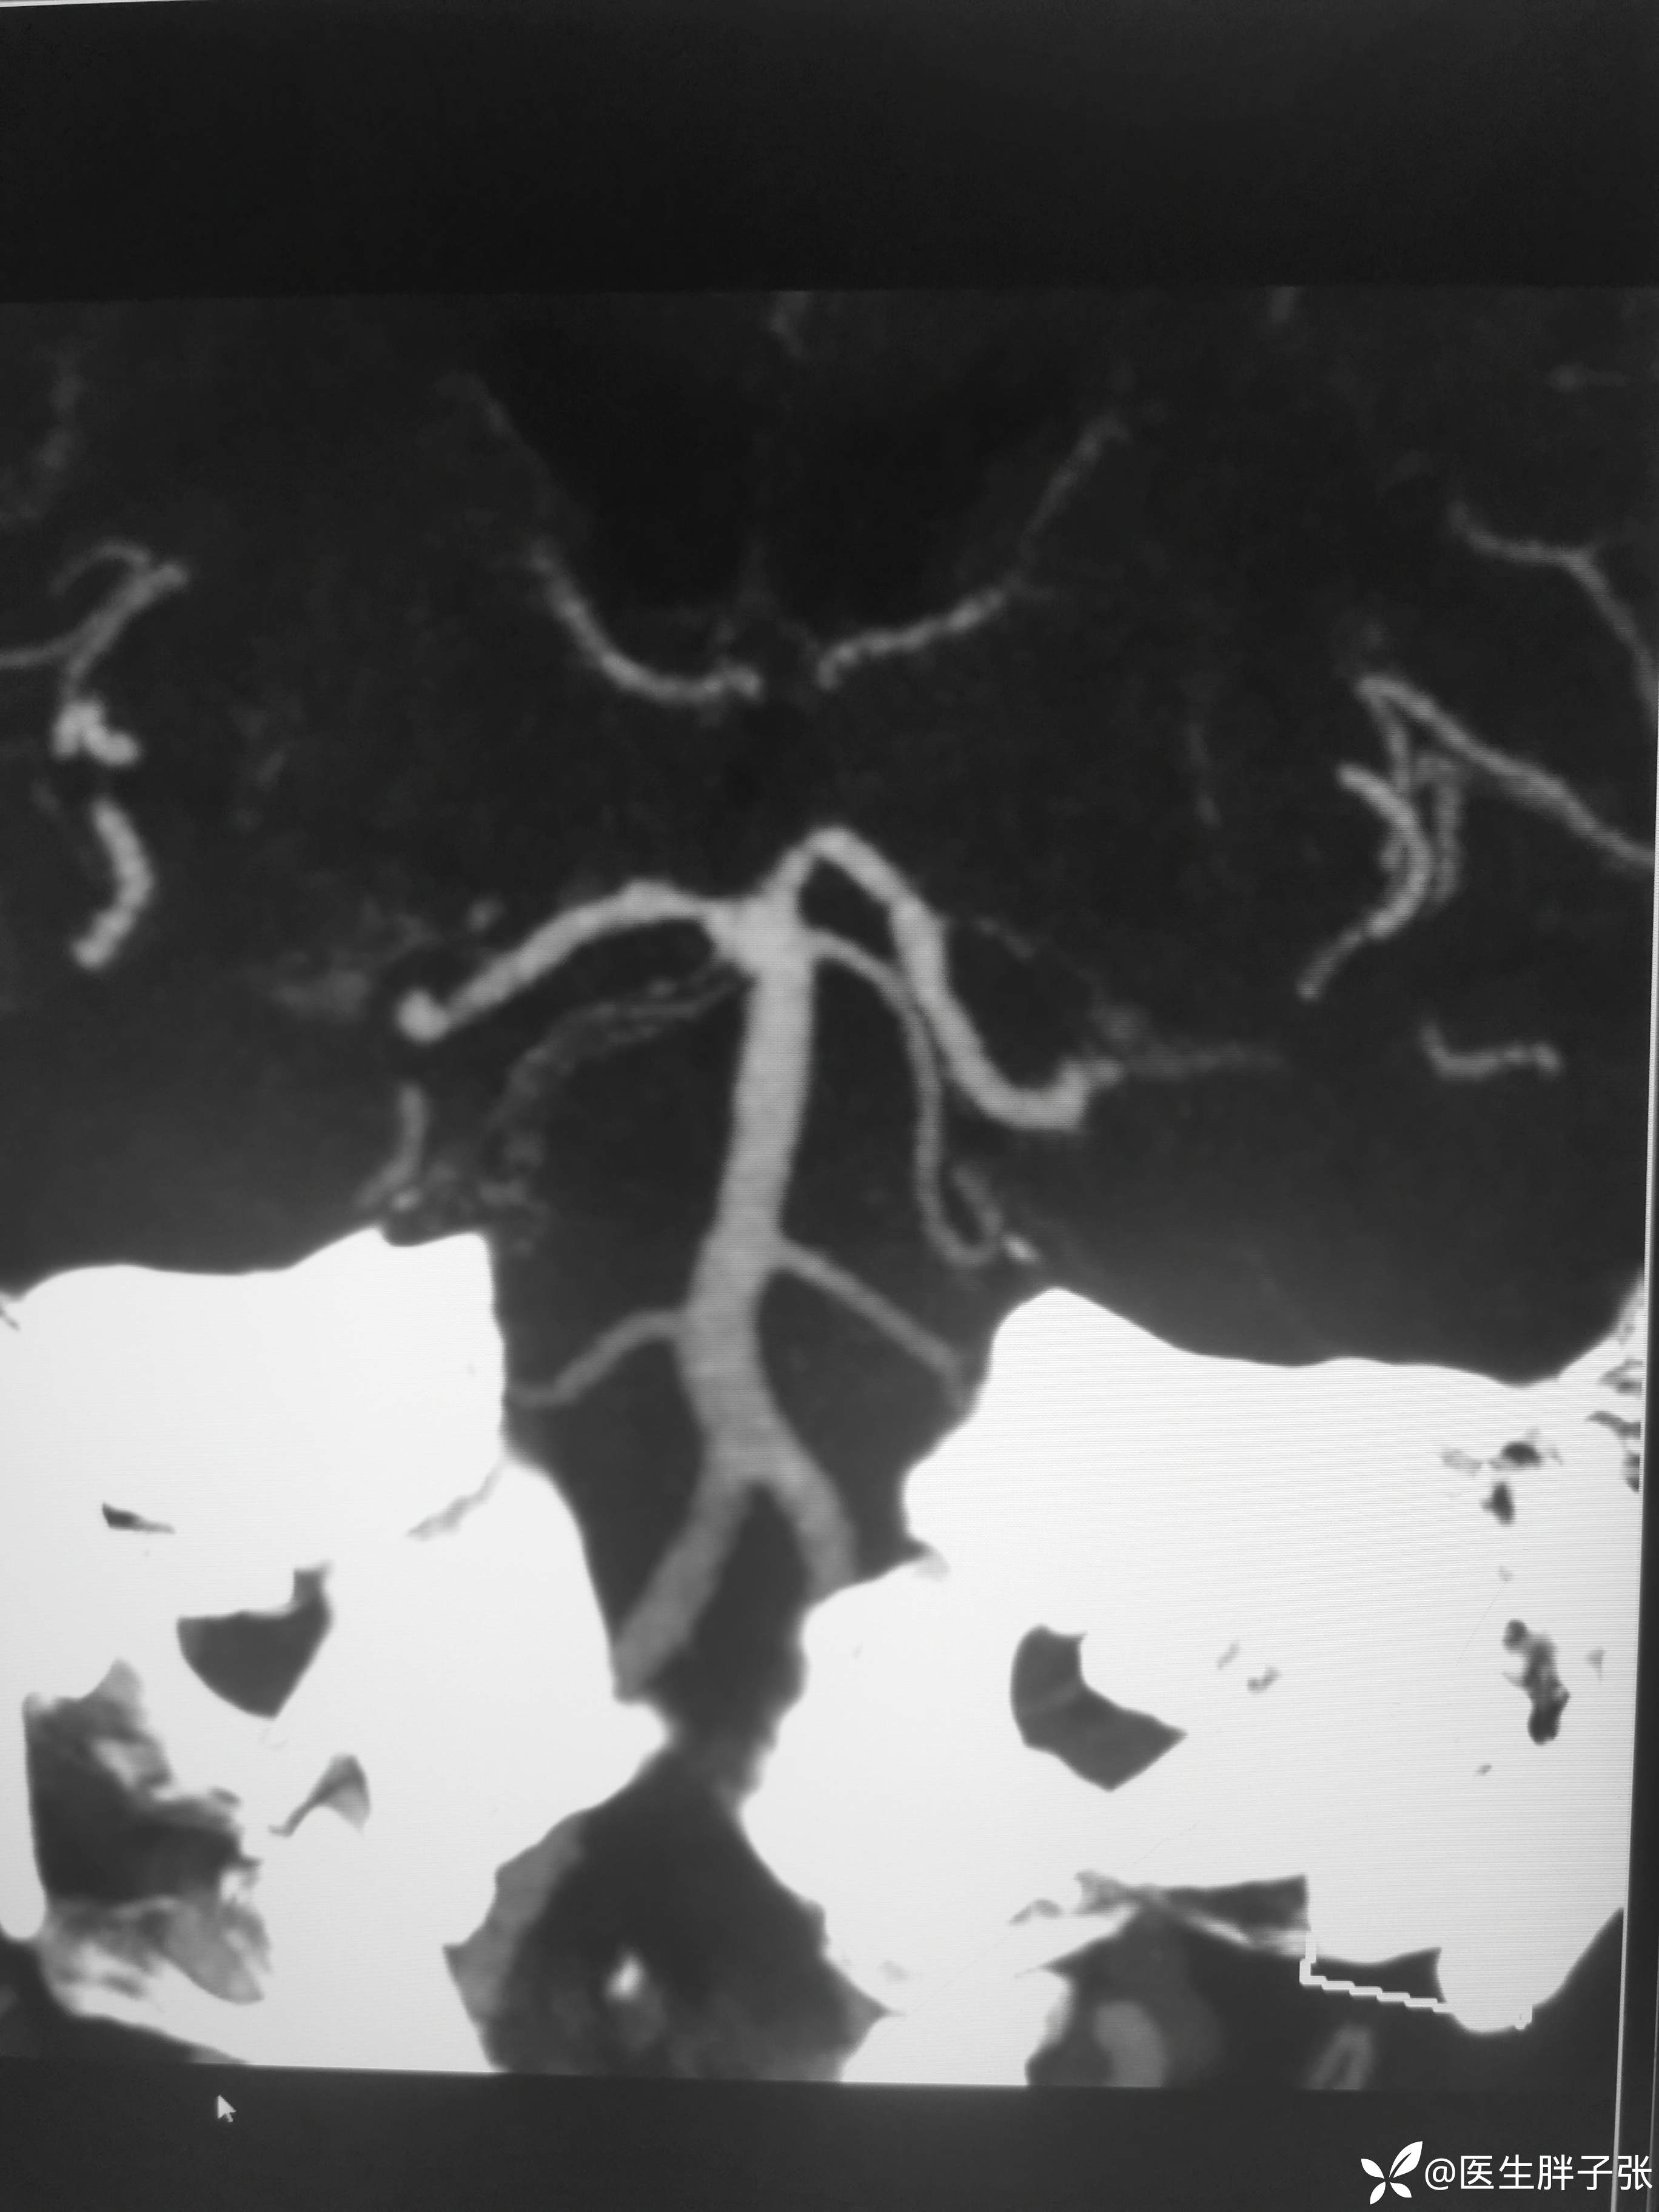

头颈部CTA